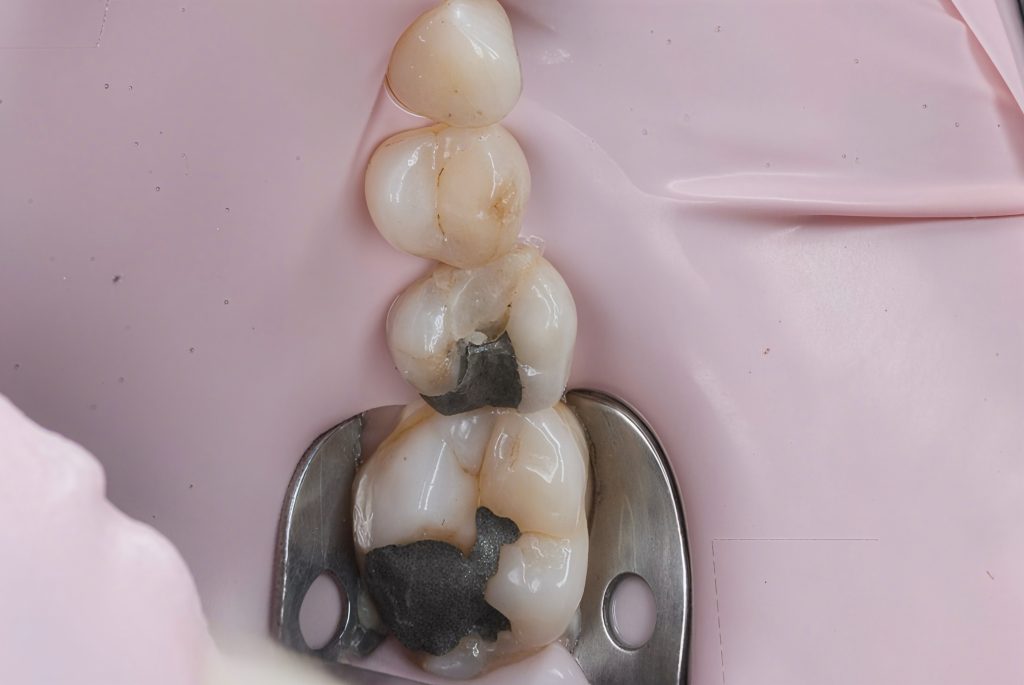

Defective composite and caries were removed in a controlled manner preserving sound enamel walls. Teflon floss ties and wooden wedges used for separation and gingival retraction (Fig 3–6).

3. Matrix System Placement

Sectional matrix system used to recreate anatomical proximal walls. Ring stabilization applied to ensure tight contact and optimal emergence profile (Fig 7–8).

- Initial caries exposure and removal

- Proximal clearance and wedge placement

- Matrix placement and isolation refinement

- Sectional ring application